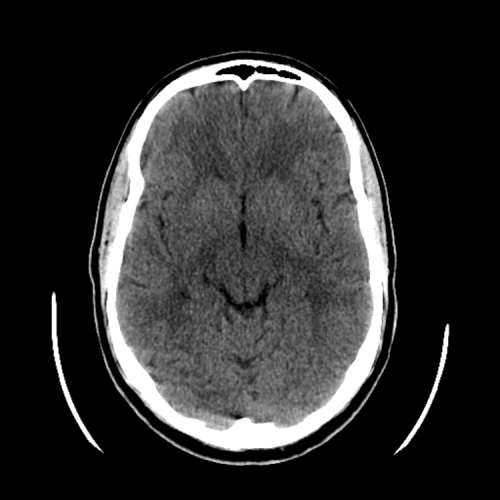

Watershed ischemia

Cardioembolic infarcts